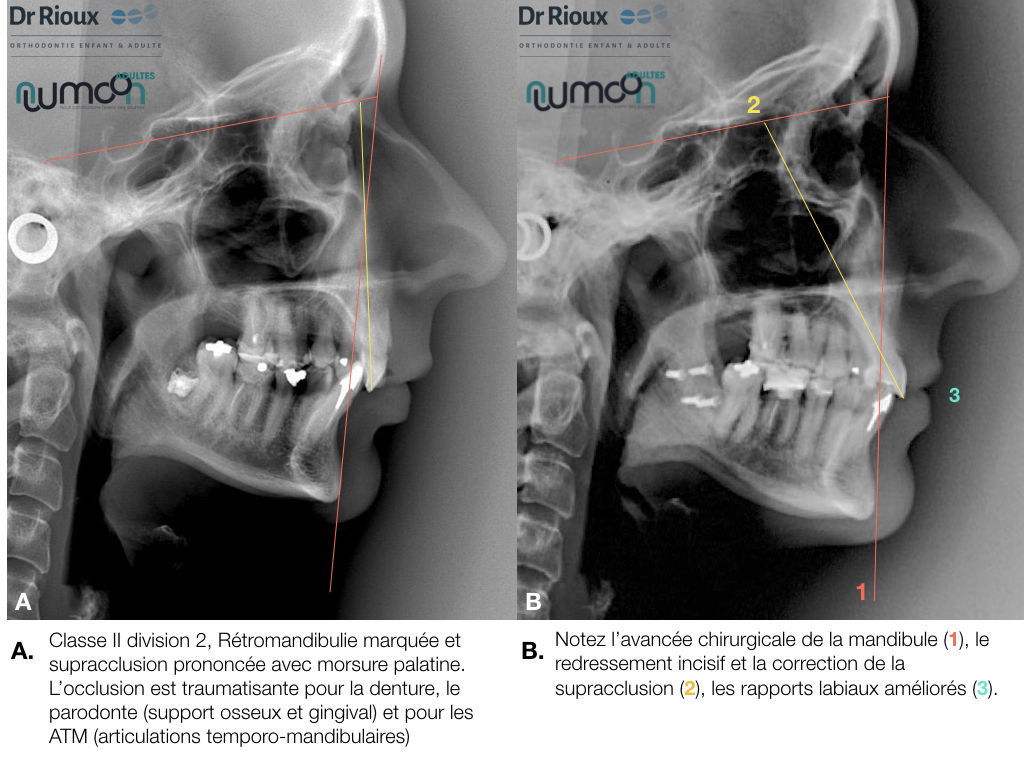

NUUMOON En images Arrêt des parafonctions (lolette, pouces, etc…) Orthodontie pédiatrique Orthopédie dento-faciale Apnée du sommeil de l’enfant (TROS) Esthétique du sourire Orthodontie et Articulation Temporo Mandibulaire (ATM) Traitement combiné ortho-chirurgicaux Traitements pluridisciplinaires Arrêt des parafonctions Effet de la lolette sur les dents Effet du pouce sur les dents Position de la langue et impact sur les dents Mieux respirer pour mieux grandir Respiration et santé Respiration et santé Sans titre.004 Orthodontie pédiatrique Conséquences ventilation orale – nuumoon ChatGPT Image 5 sept. 2025, 09_00_25 conséquences posturales de la ventilation orale Prévention canine incluse Prévention canine incluse Prévention canine incluse Dents qui s’emboitent à l’envers Dents qui s’emboitent à l’envers orthopédie dento-faciale Traitement déformation mâchoire Déformation des mâchoires : menton en avant Déformation des mâchoires : menton en avant Déformation machoire Déformation machoire Déformation machoire : machoire du bas en arrière Déformation des mâchoires : menton en avant Déformation des mâchoires : menton en avant Posture dents et mâchoire Anomalie de la mâchoire Apnée du sommeil orthodontie invisible à Genève Aligneurs transparents & bagues linguales – l’art de corriger sans rien laisser paraître Troubles de l’articulation temporo-mandibulaire et bruxisme Chirurgie orthognathique Traitements pluridisciplinaires INSIGHTS Contenu pour les enfants